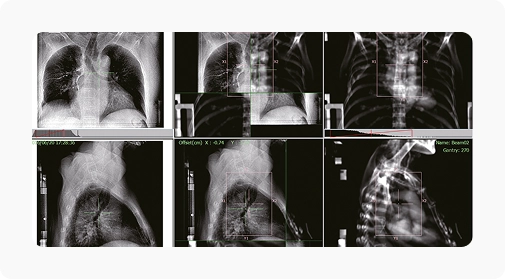

Технологии визуализации и контроля: kV CBCT, MV EPID и BPS (авторская SGRT-система LinaTech).

ИИ совмещает kV CBCT, MV EPID и BPS изображения, чтобы повысить точность облучения.

| Система визуализации | kV-CBCT , MV-EPID |

| Максимальное поле обзора CBCT [см] | 35 |

| Разрешающая способность CBCT [пара линий/см] | ≥12 |

| Разрешение матрицы детектора | 2816х2816 |